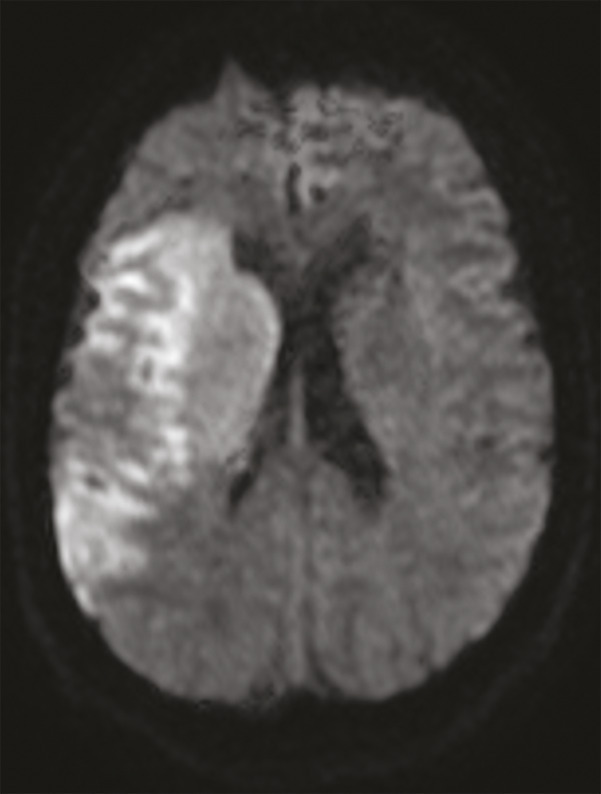

Cet homme de 41 ans, sans antécédent notable, était admis aux urgences pour une hémiplégie gauche d’apparition brutale (H3). Une angio-IRM cérébrale montrait un infarctus frontal et dans le territoire de l’artère sylvienne superficielle et profonde droit (fig. 1 ). Étant donné son jeune âge, un angioscanner des troncs supra-aortiques était réalisé, montrant une image d’éperon caractéristique de diaphragme bulbaire carotidien (fig. 2 ). Le patient était hospitalisé, mis sous traitement médical à base d’anticoagulant à dose préventive et d’antiagrégant plaquettaire en attendant la réalisation d’une artériographie avec mise en place d’un stent.